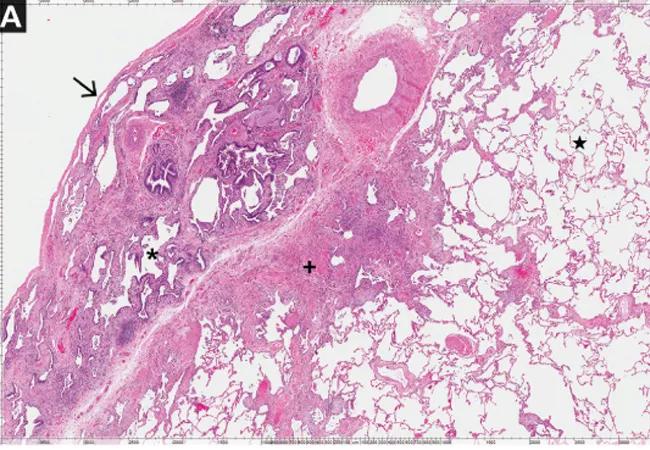

Image: Histopathologic appearance of definite pattern of usual interstitial pneumonia (UIP), a key feature of idiopathic pulmonary fibrosis. A, dense fibrosis (plus sign) with a “honeycomb” change (asterisk) is prominent at the pleural surface (arrow) juxtaposed against normal lung tissue (star) toward the center of the lung parenchyma (hematoxylin and eosin, × 40).

Usual interstitial pneumonia (UIP) is a histologic pattern observed on surgical lung biopsy specimens, characterized by fibrosis and a “honeycomb” pattern alternating with areas of normal lung parenchyma in a patchwork pattern. These abnormalities are usually subpleural and worse in the lower lobes. Inflammation is not typically seen.